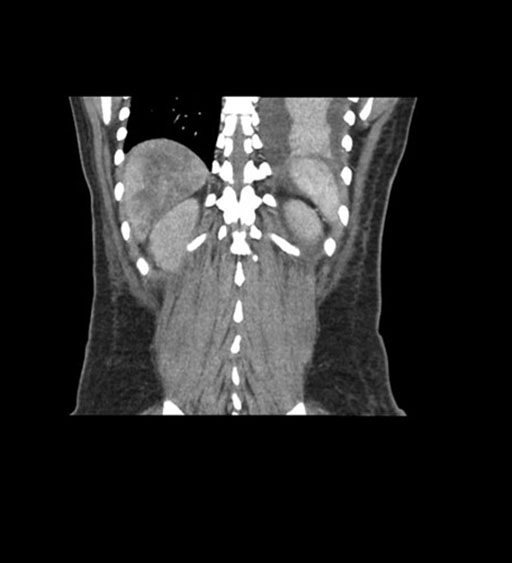

Coronal Arterial